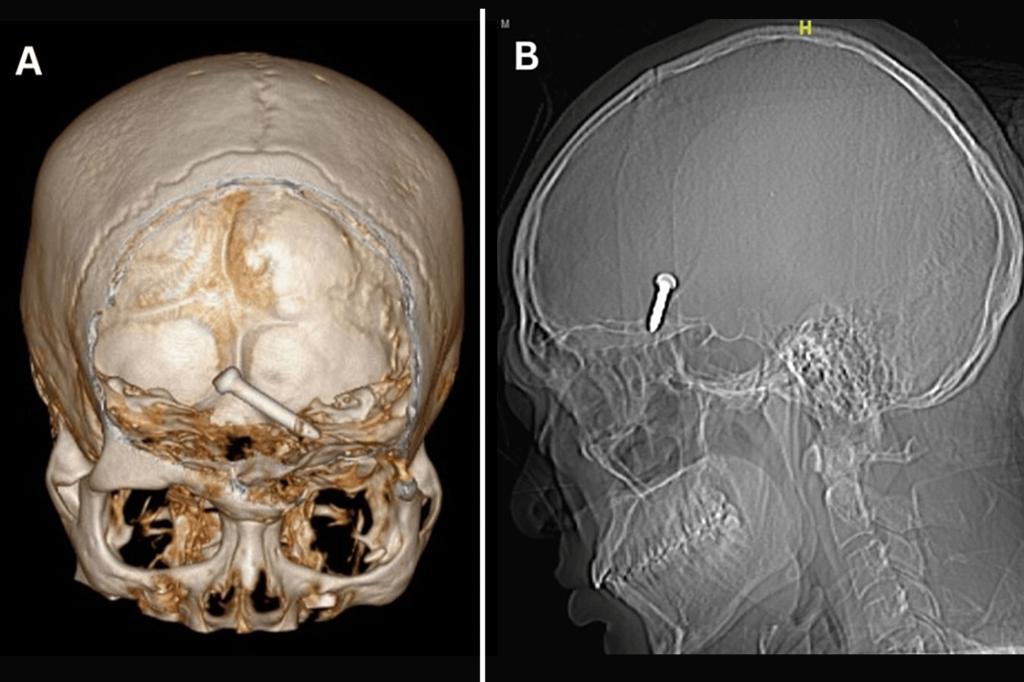

Construction worker shoots nail through eye into brain — and keeps sight

He really hit the mark. But that didn't mean it was a good thing. A construction worker miraculously survived and retained his eyesight after his nail gun malfunctioned and a 3cm nail went into his eye and into his brain. Doctors in Malaysia were able to safely remove the nail using nail-biting surgery. And a […]